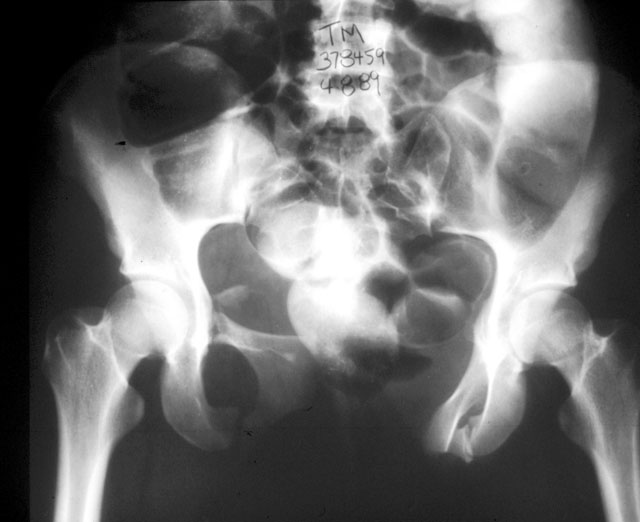

The Xrays and CT's provided show evidence of a Right sacral ala fracture, healed without significant vertical displacement or rotational abnormality. There is no evidence of external rotation through either of the SI joints. I see no evidence of there being a nonunion of a sacral fracture. I am unclear about the original purpose of the iliosacral fixation. Perhaps pre-op Xrays prior to this procedure would be helpful. In any event, there does not appear to be a substantial posterior pelvic ring deformity at this time. This is supported by the current AP pelvis which demonstrates well defined ilioischial lines bilaterally with a well positioned AP of the sacrum.

The anterior pelvic ring injury probably consisted of Bilateral superior and inferior ramus fractures as well as a fracture of the body of the pubis. The rami have united with the large anterior diastasis. I believe, therefore, that this is an isolated malunion of the anterior pelvic ring ocurring through 3 sites, the rami bilaterally and the body of the L pubis.

I enclosed a similar injury Xray. Although this patient has anterior SI widening on the left, he has the same anterior ring injury. B rami and a fx-dislocation of the symphysis.